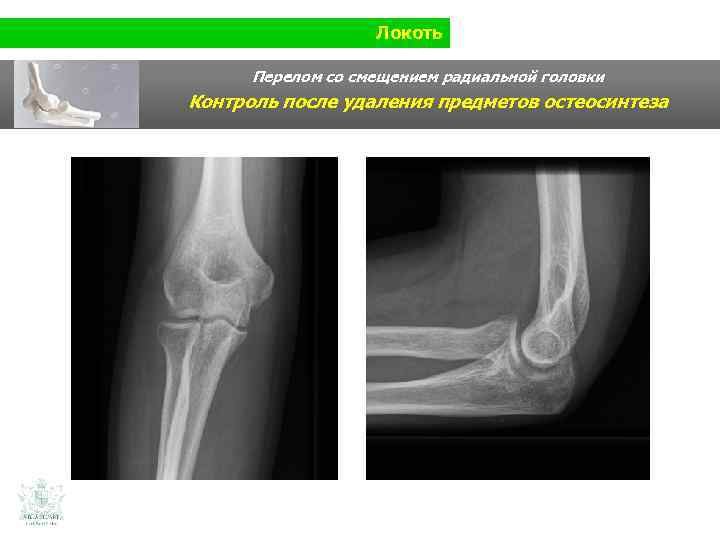

Локоть Перелом со смещением радиальной головки Контроль после удаления предметов остеосинтеза